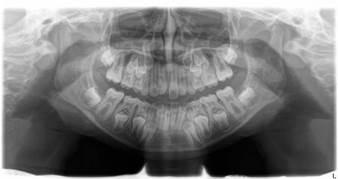

Figura 1: A radiografia panorâmica mostra o mal posicionamento dos incisivos centrais pela inserção anômala do freio labial superior

Na avaliação intraoral e de radiografia panorâmica, observou-se que havia espaçamento entre os dentes 11 e 21, mordida cruzada anterior, apinhamento dentário, dentição mista e uma inserção alta do frênulo labial superior estendendo-se para a região interincisal palatina. Anotadas as informações, fez-se o registro fotográfico autorizado e houve uma conversa com a criança, onde foi explicado a ela a importância do procedimento e como ele seria feito. Foi dito a ela que não ia sangrar, seu rosto não ficaria inchado, não doeria e a cicatrização seria mais rápida do que fazendo a cirurgia tradicional com bisturi. A menina, demonstrando aceitação, foi-lhe entregue um brinquedo como reforço positivo e ela foi liberada junto com os pais, tendo o retorno agendado para a realização da cirurgia.